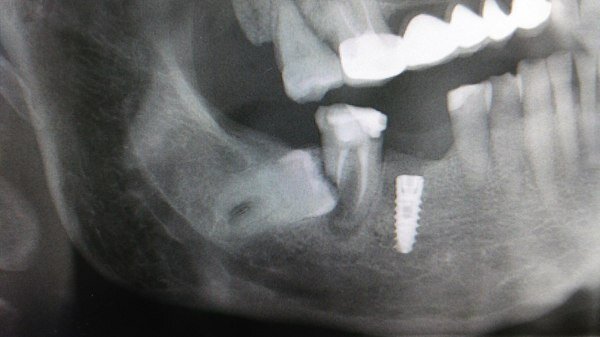

Также зубы мудрости частенько спешат удалить себе спортсмены Боевыми искусствами. Т.к. будучи в кости нижней челюсти, то больше шансов словить перелом «благодаря» этому зубу.

Но есть ситуации , когда 8ку можно оставить и даже полечить при необходимости. Например если нет 7го зуба, то можно благодаря брекетам его вытянуть на место 7го и поставить в дугу . Либо , если восьмерки прорезались ровно в дуге и в окклюзии .

Но щас тенденция, что с этими зубами возиться никто не хочет и не видит особого смысла. Иногда их удаляют сразу, не дожидаясь, пока они себя проявят.